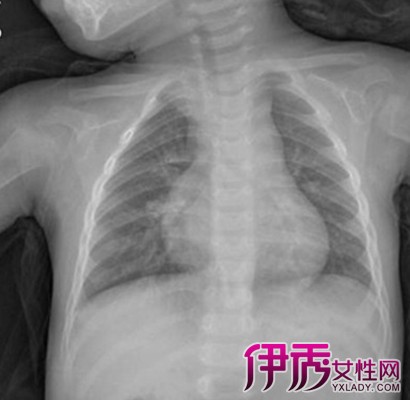

肺动脉高压早期临床症状不典型,常被误诊或漏诊,为及早获得诊断必须密切结合临床表现,体征和实验室检查,根据不同情况选用无创伤或有创伤的检查方法,首先肯定有无肺动脉高压,然后确定其严重程度,最后确定是原发性还是继发性。